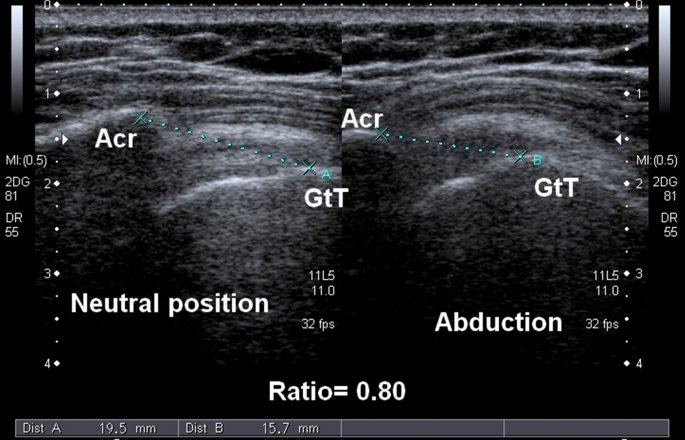

Interobserver agreement on the sonographic severity grading of shoulder impingement syndrome